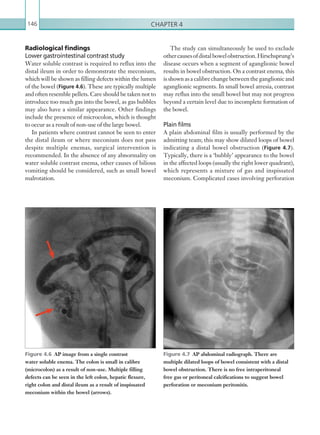

• 138.

Chapter 3116 is arachnoidgranulations, which are physiological structures that protrude into the normal dural sinus lumen. These are characteristically found laterally in the transverse sinus and in the superior sagittal sinus andappearasrounded,verywell-definedfillingdefects. If there is diagnostic uncertainty on contrast enhanced modalities, correlation with unenhanced imaging can be helpful, since arachnoid granulations often display a similar attenuation to CSF. Acute to subacute venous sinus thrombosis should be suspected on an unenhanced study where there is high attenuation corresponding to a segment of the venous sinus system (Figures 3.28, 3.29a). Common false positives on unenhanced CT include transverse sinus physiological normal anatomy of the venous sinus system is essential, and both the superficial veins and deep sinus system should be scrutinised in their entirety. The appearance of thrombus varies with age, although for the purposes of this chapter acute and subacute thrombosis are considered. Computed tomography Venous sinus thrombosis presents on contrast enhanced CT as a filling defect within the venous sinus (Figures 3.27a–c). The venous sinus system should be scrutinised in axial, sagittal and coronal planes with widewindowsettingstoavoidmissingsubtlethrombus. A common false positive on contrast enhanced CT (a) (b) (c) Figures 3.27a–c  Axial and sagittal images: IV contrast enhanced CT scans of the brain in the venous phase. Filling defects are seen within the sagittal sinus, consistent with venous sinus thrombosis (arrow). K22247_C003.indd 116 16/05/15 3:08 AM

• 139.

Neurology and non-traumaticspinal imaging 117 dominanceanddehydration,althoughthelatterusually causesglobalvenoussinushyperattenuationasopposed to a focal abnormality. The potential complications of venous sinus thrombosis must be considered. Parenchymal oedema can occur secondary to venous sinus thrombosis and presents as focal low attenuation, generally within the white matter. It should be noted that this is often reversible and may not necessarily progress to venous infarction. Indirect signs include atypical haemorrhage and oedema that does not correspond to an arterial territory.Bilateralthalamicoedemaishighlysuggestive of thrombosis of the deep venous system (internal cerebral veins, vein of Galen and straight sinus); if this is seen on unenhanced imaging, further contrast enhanced imaging should be performed to assess for venous sinus thrombosis (Figure 3.29b). Secondary haemorrhage can also be seen, which differs in its morphologyfromatypical‘hypertensive’ haemorrhage. Figure 3.28  Axial image: unenhanced CT scan of the brain. The anterior portion of the superior sagittal sinus is hyperdense (arrow) compared with the corresponding posterior segment, which is suspicious of a venous sinus thrombus in the anterior portion. Figure 3.29a  Axial image: unenhanced CT scan of the brain. High attenuation thrombus is seen within the internal cerebral veins (arrow). Figure 3.29b  Axial image: unenhanced CT scan of the brain. In addition to the thrombosis of the internal cerebral veins seen in Figure 3.29a, there is low attenuation change affecting both thalami, consistent with infarction. (a) (b) K22247_C003.indd 117 16/05/15 3:08 AM

• 140.

Chapter 3118 (Table 3.12).When seen in association with venous sinus thrombosis, increased parenchymal signal on T2 weighted and FLAIR sequences is suggestive of associated oedema. Corresponding restricted diffusion on diffusion weighted sequences is indicative of complicating infarction (Figures 3.31–3.33a, b). Key points • CT venography is the imaging modality of choice for diagnosing venous sinus thrombosis in the out of hours setting. • The hallmark of venous sinus thrombosis on contrast enhanced CT is a filling defect in the venous sinus system. Report checklist • Document the venous sinuses involved. • Presence or absence of any complications of venous sinus thrombosis (e.g. oedema, infarction or haemorrhage). Reference Stam J (2003) Cerebral venous and sinus thrombosis: incidence and causes in ischemic stroke. Adv Neurol 92:225–232. Typical characteristics include irregular, flame- shaped haemorrhage involving both the cortex and subcortical regions. The identification of this type of ‘atypical’ haemorrhage on a unenhanced study should always prompt suspicion of venous sinus thrombosis. A common cause of venous sinus thrombosis is sinusitis. The paranasal air spaces and mastoid air cells should be well aerated – any opacification of these spaces is suggestive of sinusitis. Magnetic resonance imaging As with CT, venous sinus thrombosis is suggested on contrast enhanced and time of flight MRI sequences as a filling defect within the venous sinus (Figure 3.30). Interpretation of time of flight MRI can be more challenging than contrast enhanced imaging. A common false positive is flow gap phenomenon, which occurs when the plane of acquisition is not perpendicular to the sinus (for example axial image acquisition of the superior sagittal sinus). Knowledge ofthislimitation,alongwithcorrelationwithadditional sequences, can help prevent this pitfall. The venous sinus system should also be scrutinised on T1 and T2 weighted sequences, although the precise signal characteristic of the thrombus is dictated by its age Figure 3.30  3-D reconstruction of a MR venogram sequence. No flow is seen within the straight sinus owing to occlusion as a result of venous sinus thrombosis. AGE OF THROMBUS T1 SIGNAL T2 SIGNAL Acute (0–5 days) Isointense Hypointense Subacute (6–15 days) Hyperintense Hyperintense Chronic (15 days) Isointense Isointense/hypointense Table 3.12 MRI signal characteristics of an ageing thrombus. K22247_C003.indd 118 16/05/15 3:08 AM